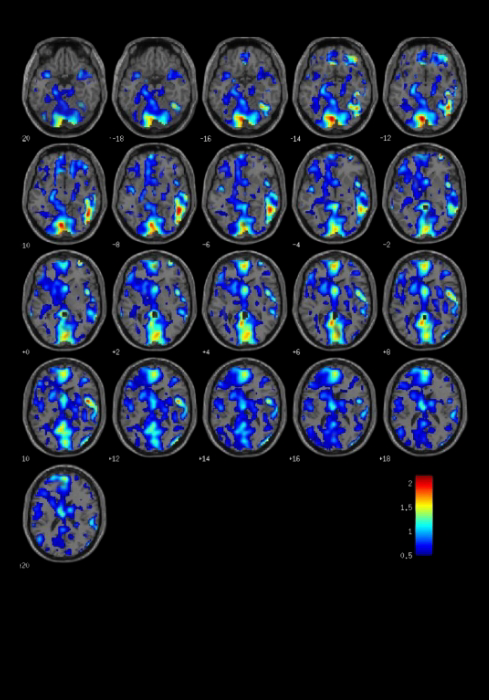

This whole-brain activation is verified by fMRI studies, showing up to 1500% more brain activity during reading sessions with Infinite Mind compared to reading alone.